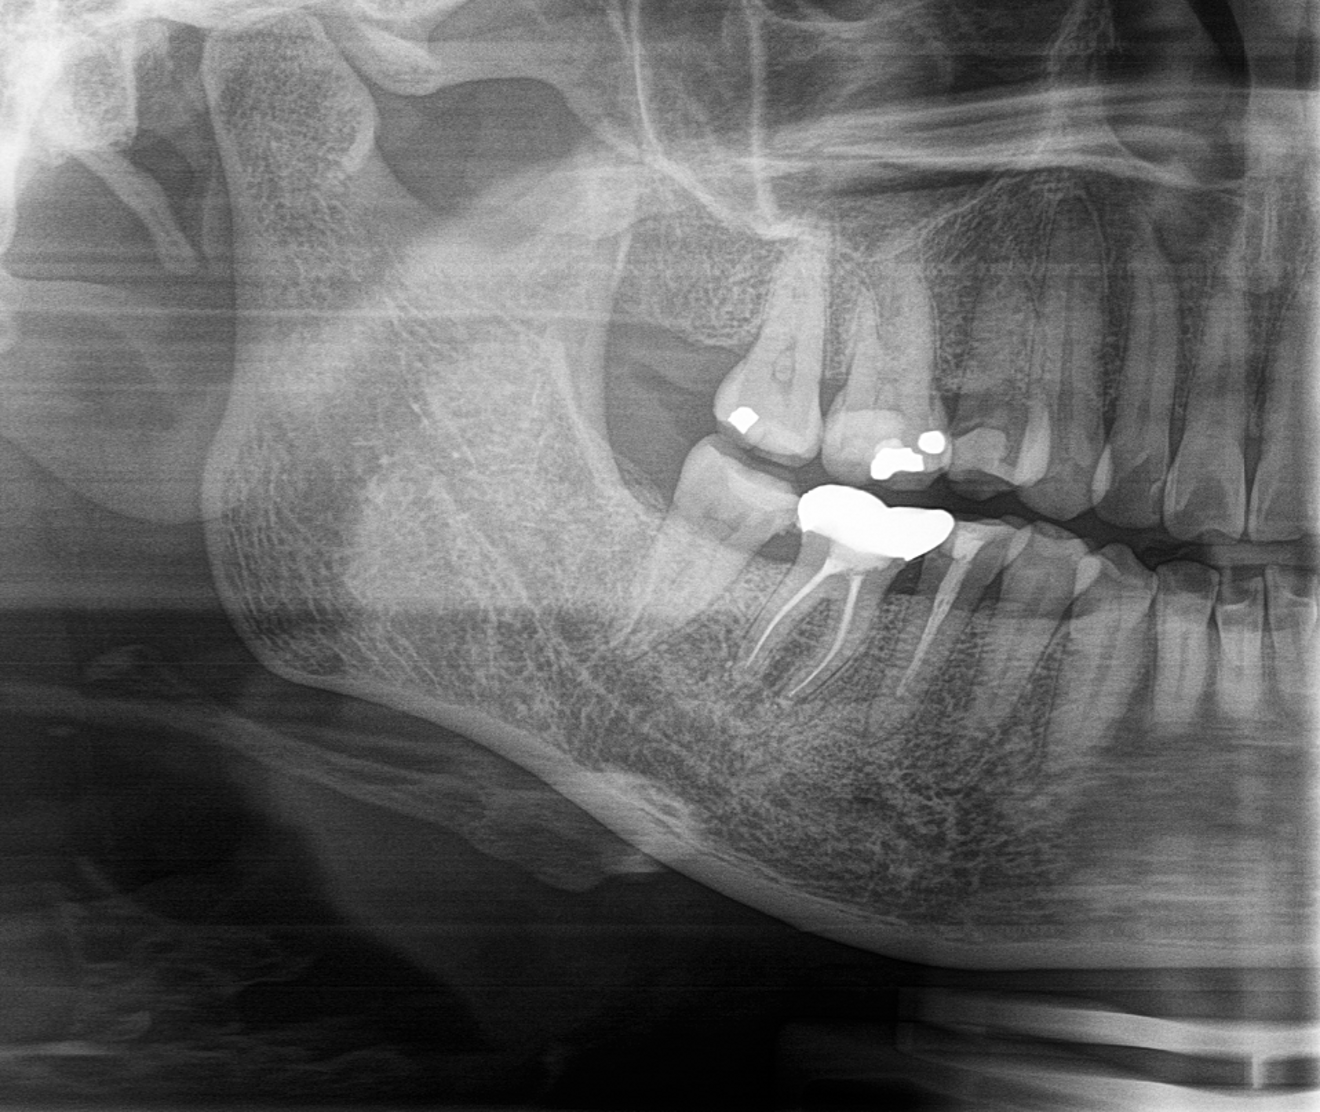

Fig. 3: Pulp chamber after irrigation with R-SWEEPS.

The R-SWEEPS final irrigation protocol was performed at the end of instrumentation and consisted of two cycles of 17% EDTA activated by R-SWEEPS for 30 seconds for each activation period with 30 seconds of resting time in between, rinsing with distilled water activated by R-SWEEPS for 30 seconds, and then three cycles of 5% NaClO activated by R-SWEEPS for 30 seconds for each activation period and a resting time of at least 30 seconds in between. After drying the canals (Fig. 3), Odontopaste (Australian Dental Manufacturing), a zinc oxide-based root canal paste with 5% clindamycin hydrochloride and 1% triamcinolone acetonide, was placed, followed by a temporary filling (Fig. 4).